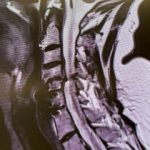

(Fig. 3) AP and Lateral cervical X-ray 6 months from surgery demonstrates a stable construct and alignment.

Postoperatively the patient had an uneventful course with relief of her right arm pain and stable construct (Fig. 3) at follow up at 6 months.